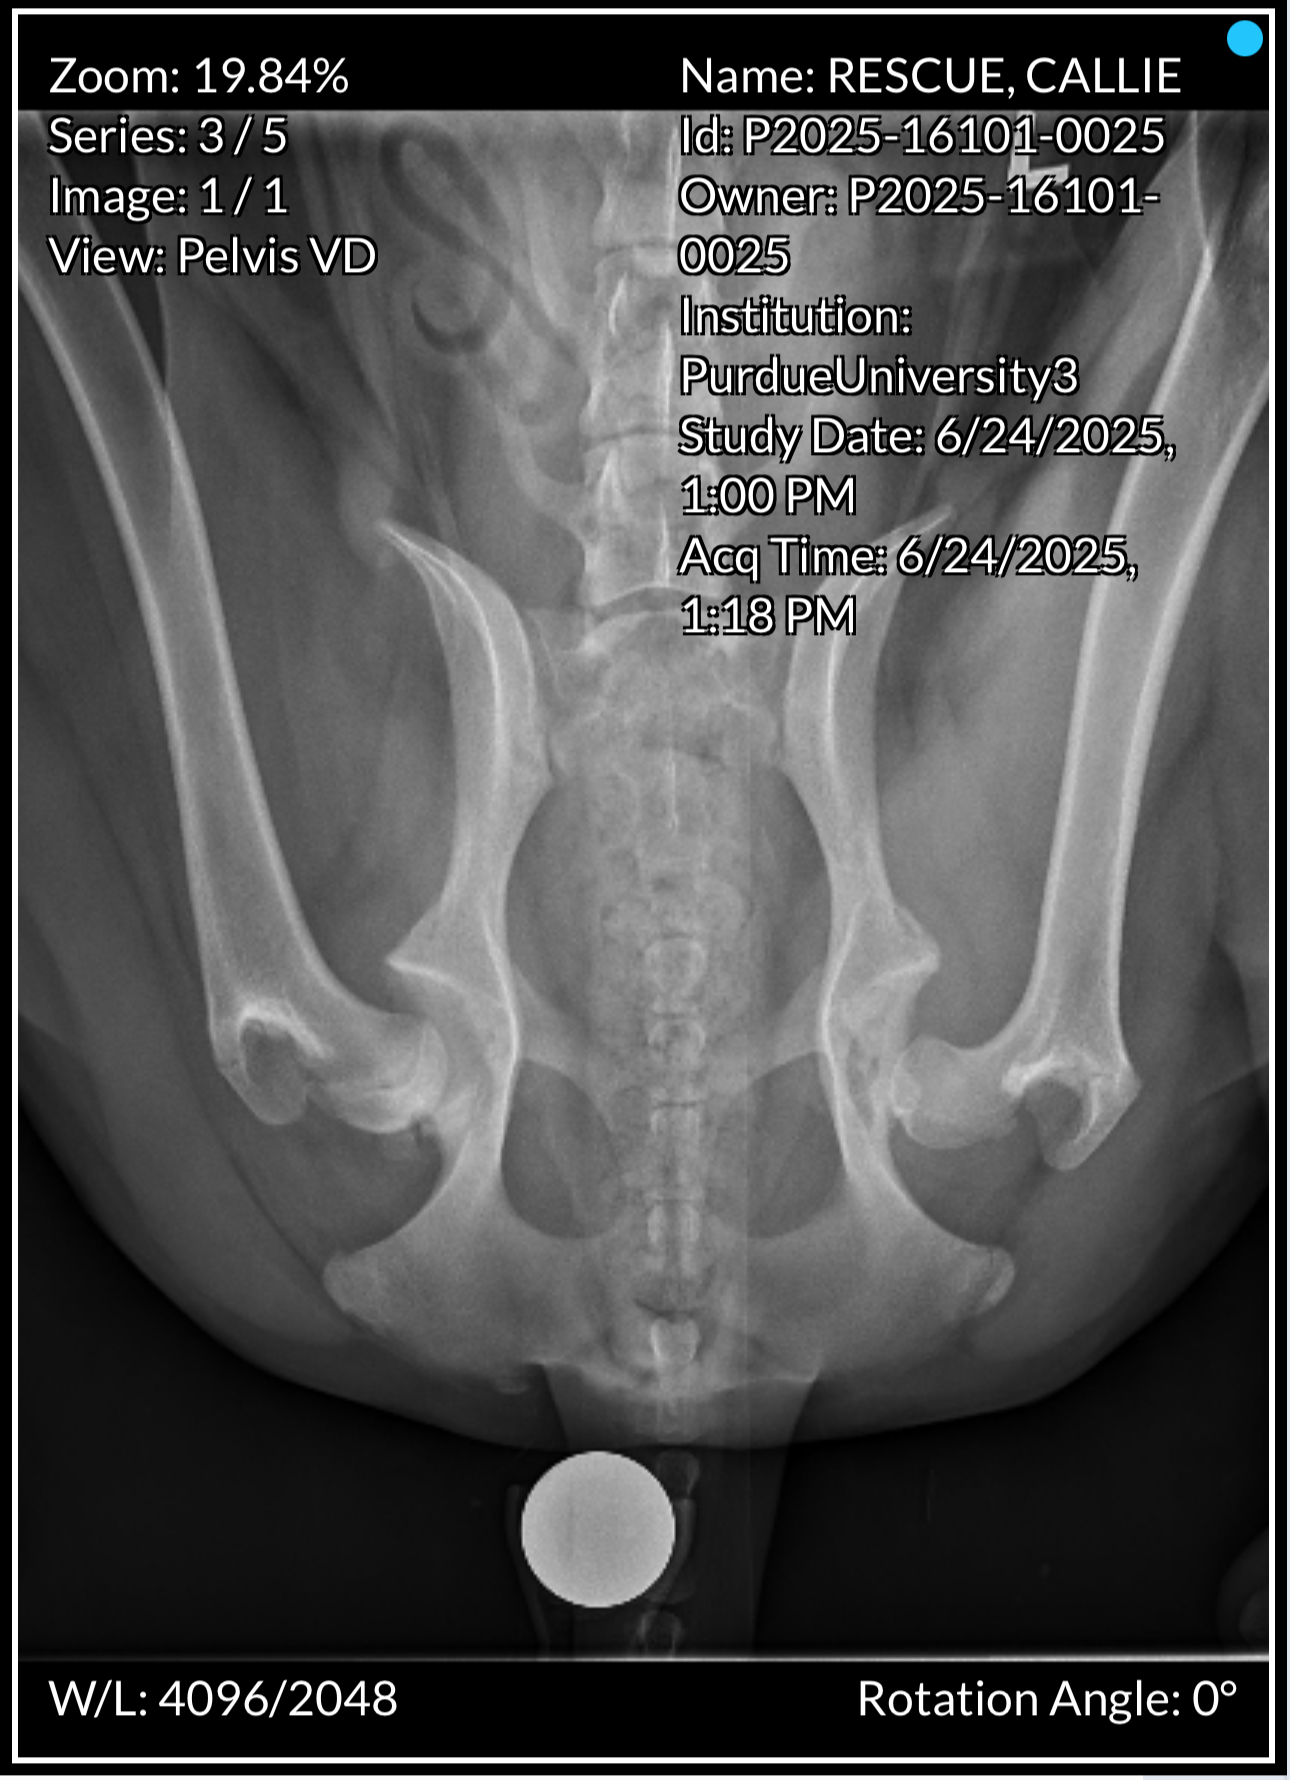

Cali came to NEOCR in May 2025 at just 9 months old. Poor breeding left her with severe hip dysplasia, and she needed major surgery on both hips—care her owner could not afford. Surrendering Cali to NEOCR was a difficult but loving choice that gave her the chance at a healthy future.

After multiple evaluations, NEOCR sent Cali to Purdue University for treatment, where a board member in Indiana fostered her through recovery. Her first hip replacement in July 2025 was complex and unfortunately failed, requiring a corrective FHO surgery and a six‑month recovery. On January 8, 2026, she underwent a second successful FHO on her right hip. She is now healing well and expected to be fully recovered within 6–12 weeks.